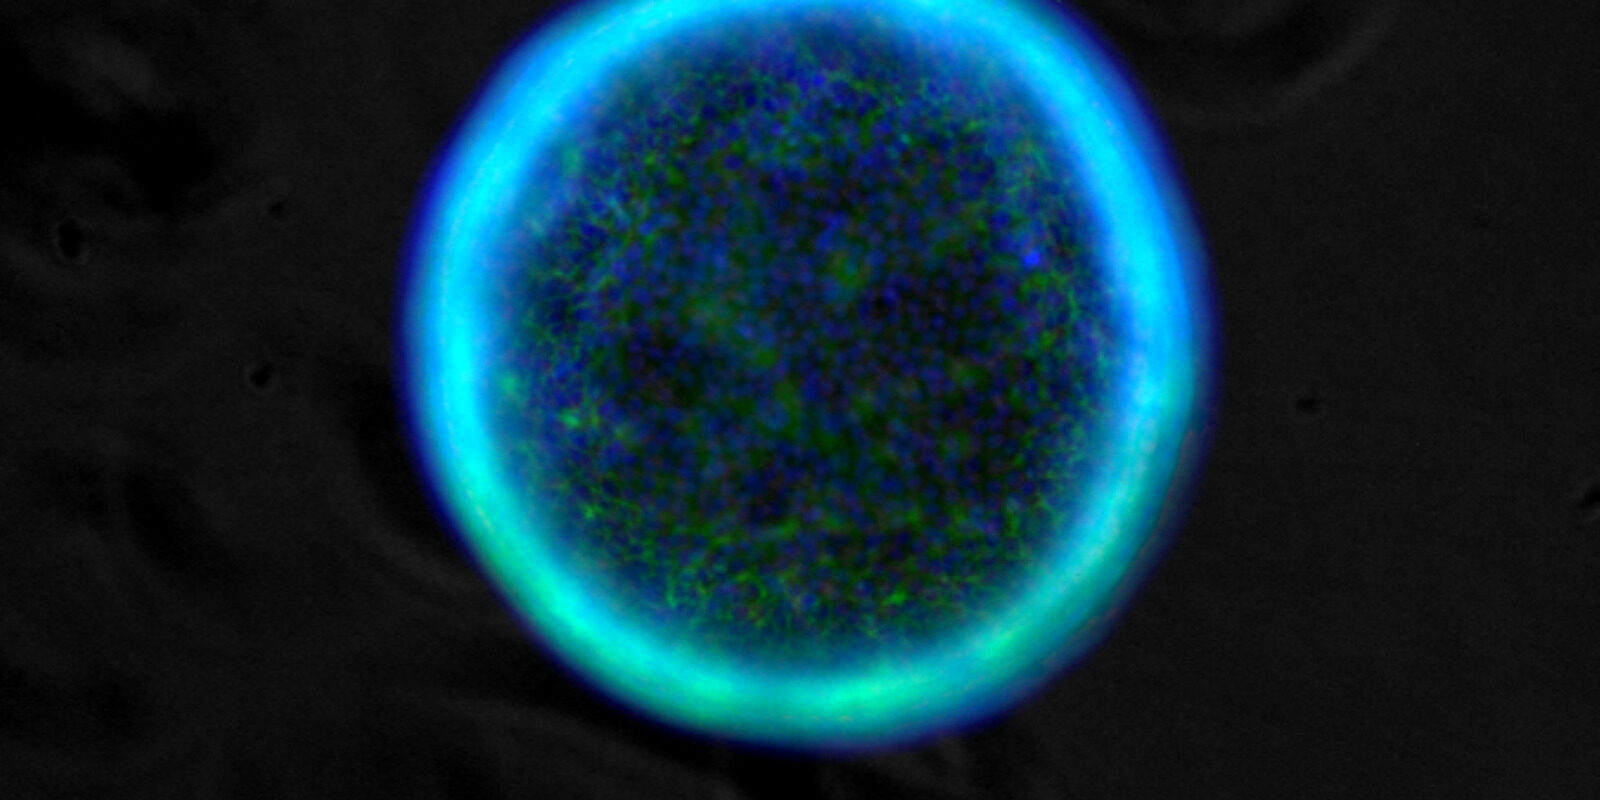

A TU PER TU CON LE CELLULE BUONE E “CATTIVE”

Attraverso giochi e laboratori aperti per tutte le età, descriveremo le differenze tra cellule normali e tumorali, illustrando in modo divulgativo e interattivo le loro caratteristiche, i processi alla base della trasformazione di una cellula verso la tipologia tumorale (autofagia, alterazioni del microbiota e del sistema immunitario) e gli stili di vita che possono influenzare il corretto mantenimento della funzionalità cellulare. Il percorso si svilupperà attraverso la creazione di semplici modelli sperimentali per studiare i tumori in provetta, osservazioni al microscopio di cellule sane e tumorali, realizzazione di modelli divulgativi della cellula e di corretti stili di vita per preservare i processi alla base della normale funzionalità cellulare, piccoli esperimenti, questionari sulle abitudini alimentari, descrizione delle strategie anti-cancro utilizzate nella ricerca farmacologica e degli effetti della presenza del cancro.